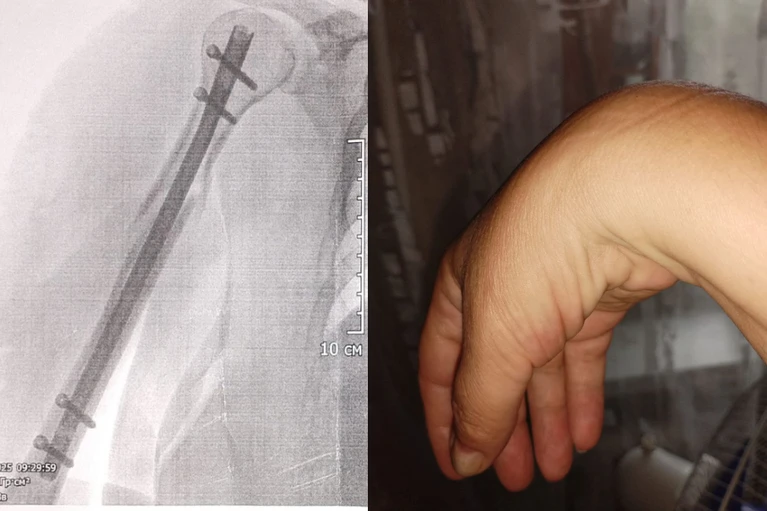

- Кафельный пол был скользкий, я запнулась на коврике и начала падать. По инерции я выбросила вперед правую руку, проехала на скользком полу и врезалась рукой в стену и потеряла сознание. Когда очнулась. рука повисла плетью, - рассказала КП-Новосибирск Оксана.

- 1 апреля мне сделали первую операцию, установили титановый стержень с болтами и закрепили кости плеча. Вторая операция была через две недели: устраняли посттравматический невроз. Сказали, что все прошло нормально. Но правая кисть у меня осталась парализована с момента травмы: я не могла работать, даже есть было трудно, - говорит Оксана.

- После перелома плечевой кости и операции по синтезу кости у Оксаны повисла кисть и перестали разгибаться пальцы. Это произошло из-за повреждения лучевого нерва: у пациентки были парализовало мышцы, которые отвечают за сгибание и разгибание пальцев. Коллеги из Новосибирска успешно провели ей остеосинтез, прежде чем она попала к нам, - сообщил Андрей Байтингер, врач-нейрохирург Томского НИИ Микрохирургии. – Но на нашей операции мы обнаружили выраженное рубцовое сращение нерва с металлом и окружающими тканями и решили провести невролиз лучевого нерва.